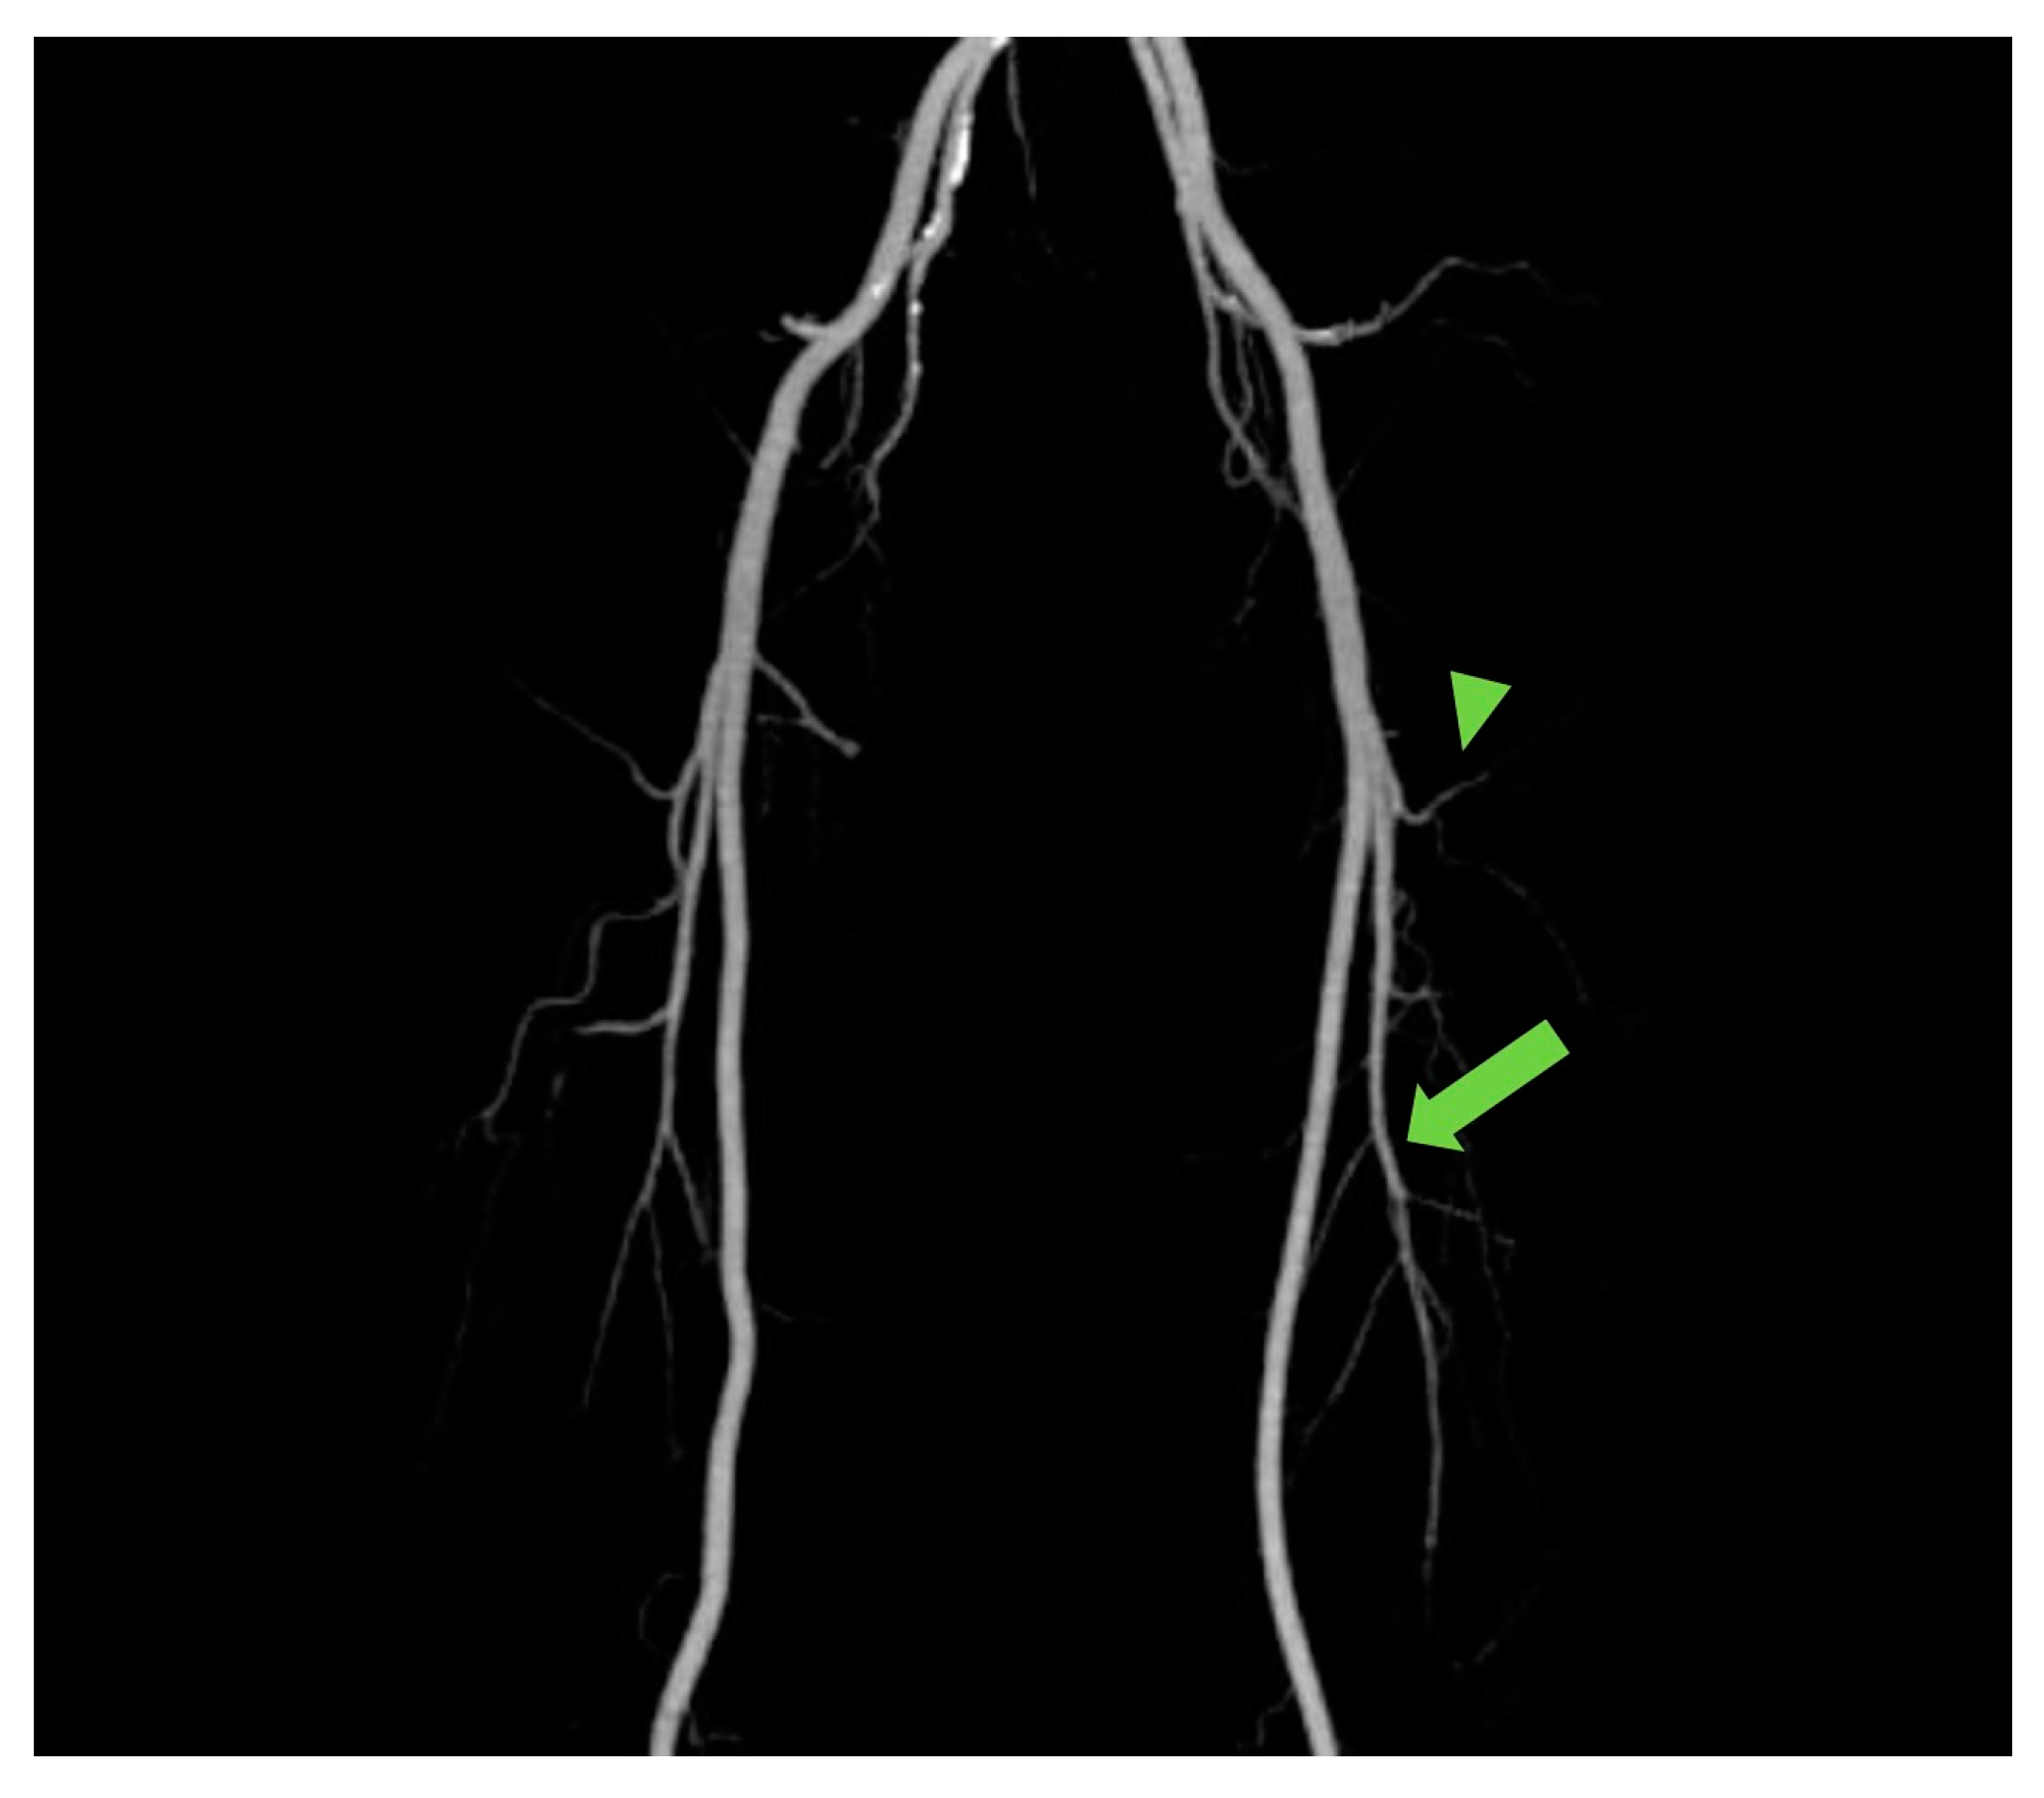

The ALT free flap is reliable and versatile owing to the appropriate diameter of its vascular pedicle and harvestability as a “freestyle flap”. In addition, it enables two-team approaches in the head and neck region, which can shorten the total operation time [8,9,10,11,12]. However, despite these advantages, there are clear drawbacks such as muscle-penetrating musculocutaneous perforators, and the varied branching pattern of LCFA, resulting in time-consuming dissection [13]. To overcome these hassles, the anatomical studies of branching patterns among ethnicities have been conducted [10,11,14], such knowledge regarding anatomic variation of the branching patterns potentially aiding planning and flap harvesting. However, with CTA, the branching pattern of each individual’s LCFA can be seen at a glance in maximum intensity projection (MIP) [15] (Figure 4). Moreover, CTA can provide individualized information regarding the location, number, length, and course of perforators in each patient, actually aiding in planning and designing the reconstruction and harvesting of the flap [6,16].

Figure 4.

The maximum intensity projection (MIP) reconstruction showing the anatomy and course of perforators from transverse branch (arrowhead) and descending branches (arrow).